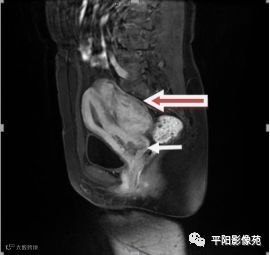

MRI表现

T2矢状位

(宫腔内见金属节育环伪影)宫颈区见不规则形等T1稍长T2信号软组织肿块,DWI序列呈明显高信号,大小约为3.87cmX2.64cm,双侧宫颈基质低信号环连续性中断,病灶向子宫右后上方生长,周围脂肪间隙模糊,增强扫描明显强化,强化程度低于子宫及宫颈实质;子宫后方、子宫直肠间隙见不规则形长T1长T2信号软组织肿块,DWI序列呈高信号,大小约10.12cmX4.82cmX10.29cm,病灶呈分叶状,向下方生长与宫颈分界不清,与直肠分界尚清,增强扫描明显不均匀强化。